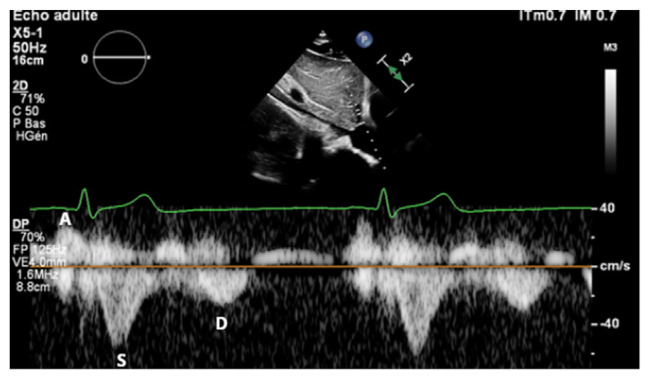

Abstract Image